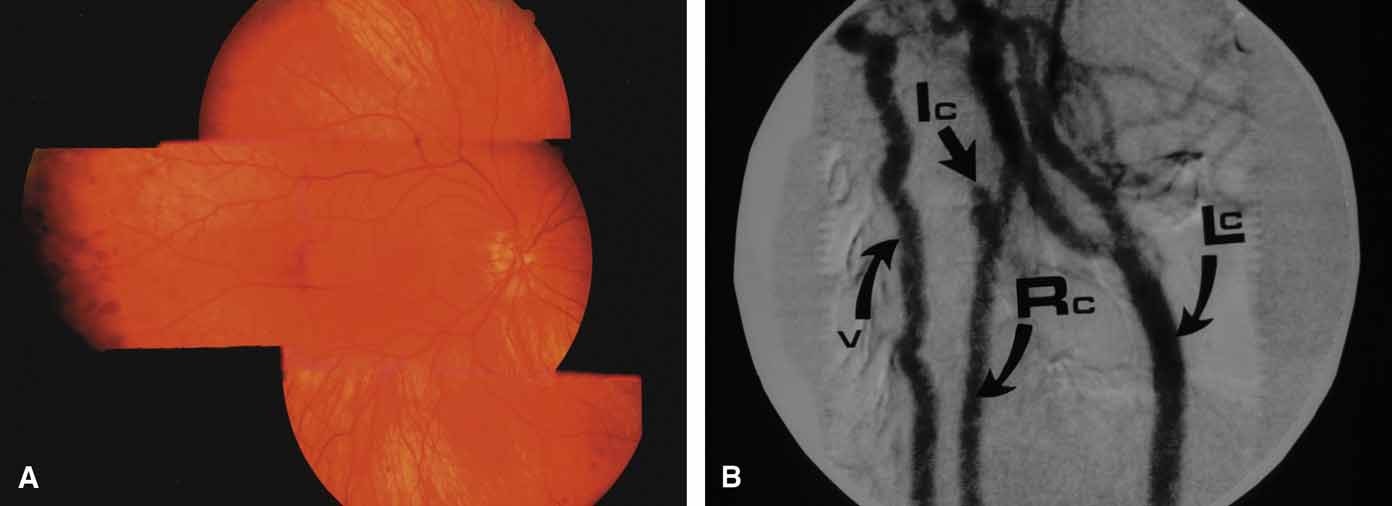

Central Retinal Vein Occlusion (CRVO)

The vascular thrombosis in central retinal vein occlusion is believed to lie within the optic nervehead at the level of the lamina cribrosa or behind where the vein and the artery share a common adventitial sheath.127 Rarely, an initial period of hypotony may develop after an acute central retinal vein occlusion.128 If major retinal capillary compromise is present,129 iris neovascularization may develop within 1 to 3 months and produce peripheral angle synechiae and angle closure. Ischemic central retinal vein occlusions represent less than one-third of all central venous obstructions and are characterized by multiple cotton-wool spots and a poor visual acuity, typically less than 20/200 (6/60) (Fig. 21).

Fig. 21 Ischemic central retinal vein obstruction. A. Heavy intraretinal hemorrhages, cotton-wool spots, and vision of 20/400 (6/120). B. Fluorescein angiogram clearly demonstrates severe loss of capillary bed perfusion.

Although cotton-wool spots represent infarcts of the nerve fiber layer and may be a clinical sign of ischemia, any eye with a central retinal vein occlusion should be monitored with monthly slit lamp and gonioscopic exams. The onset of neovascularization of iris or angle warrants pan retinal photocoagulation to try to prevent neovascular glaucoma.130,131 Between 10% and 20% of eyes with central retinal vein occlusion may convert from an initial nonischemic angiographic picture to ischemia, especially if the initial vision is poor. The greatest risk of conversion to ischemia is found 1 to 3 months following the occlusion but can occur even later. Nonischemic occlusions (Fig. 23) should be followed closely during this time period.

Fig. 23 Nonischemic central retinal vein obstruction. A. Dilated, tortuous veins, minimal intraretinal hemorrhages, and 20/40 (6/12) vision. B. Fluorescein angiogram showing minimal damage to capillary bed. Despite the lack of ischemic capillary damage on the present study, up to 20% of patients may convert to the ischemic type, necessitating careful follow-up examinations.